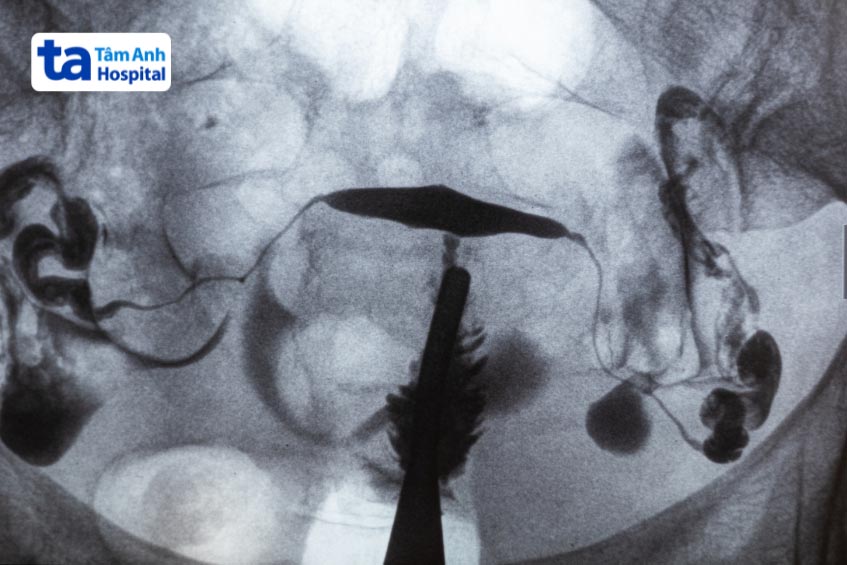

Chụp HSG giúp phát hiện các bất thường vòi trứng, tử cung, từ đó đưa ra hướng điều trị phù hợp

Chỉ định chụp X-quang vòi trứng giúp đánh giá tình trạng sức khỏe sinh sản, được áp dụng cho những trường hợp gặp khó khăn trong việc thụ thai tự nhiên, tiền sử sảy thai liên tiếp hoặc vô sinh không rõ nguyên nhân. Kỹ thuật X-quang tử cung vòi trứng (HSG) có khả năng phát hiện các bất thường gây vô sinh như dị tật tử cung (tử cung đôi, tử cung hai sừng), tắc nghẽn/ứ dịch ống dẫn trứng, bất thường trong buồng tử cung như u xơ tử cung, polyp hoặc dính buồng tử cung sau phẫu thuật.